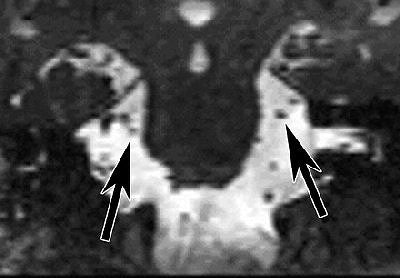

![]() |

| Coronal reformatted image of the brain. Constructive interference in steady state (CISS) MR image (17/8.3) at the level of the ambient cistern reveals trigeminal nerve on right (left arrow) is smaller than trigeminal nerve on left (right arrow). Figure 1, Erbay SH, Bhadelia RA, O'Callaghan M, et al. "Nerve atrophy in severe trigeminal neuralgia: Noninvasive confirmation at MR imaging -- initial experiences." Radiology 2006; 238:689-692. |

However, Erbay said that he believes visible TN markers do exist, and he's currently engaged in an ongoing trial to confirm TN with MRI. Erbay and colleagues published some early results of their work last year and found that trigeminal nerve atrophy can be depicted noninvasively with gadolinium-enhanced MRI (Radiology, February 2006, Vol. 238:2, pp. 689-692).